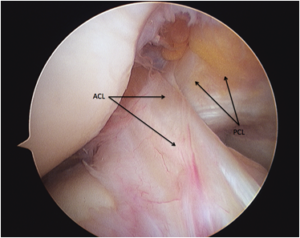

The anterior cruciate ligament (ACL) is a 3-4cm long band of fibrous tissue that connects the femur (thigh bone) to the tibia (shin bone). It helps stabilise the knee joint when performing twisting actions. The cruciate ligament is usually not required for normal daily living activities, however, it is essential in controlling the rotation forces developed during side stepping, pivoting and landing from a jump.

Anatomic placement of an anterior cruciate ligament (ACL) graft is critical

to the success and clinical outcome of ACL reconstruction. Anatomic ACL graft placement is defined as positioning the ACL femoral and tibial bone tunnels at the center of the native ACL femoral and tibial attachment sites.

In the Anatomical ACL reconstruction technique, which is used in most advanced centres of the world, we use an accessory anteromedial portal with the knee flexed to 120 degrees.